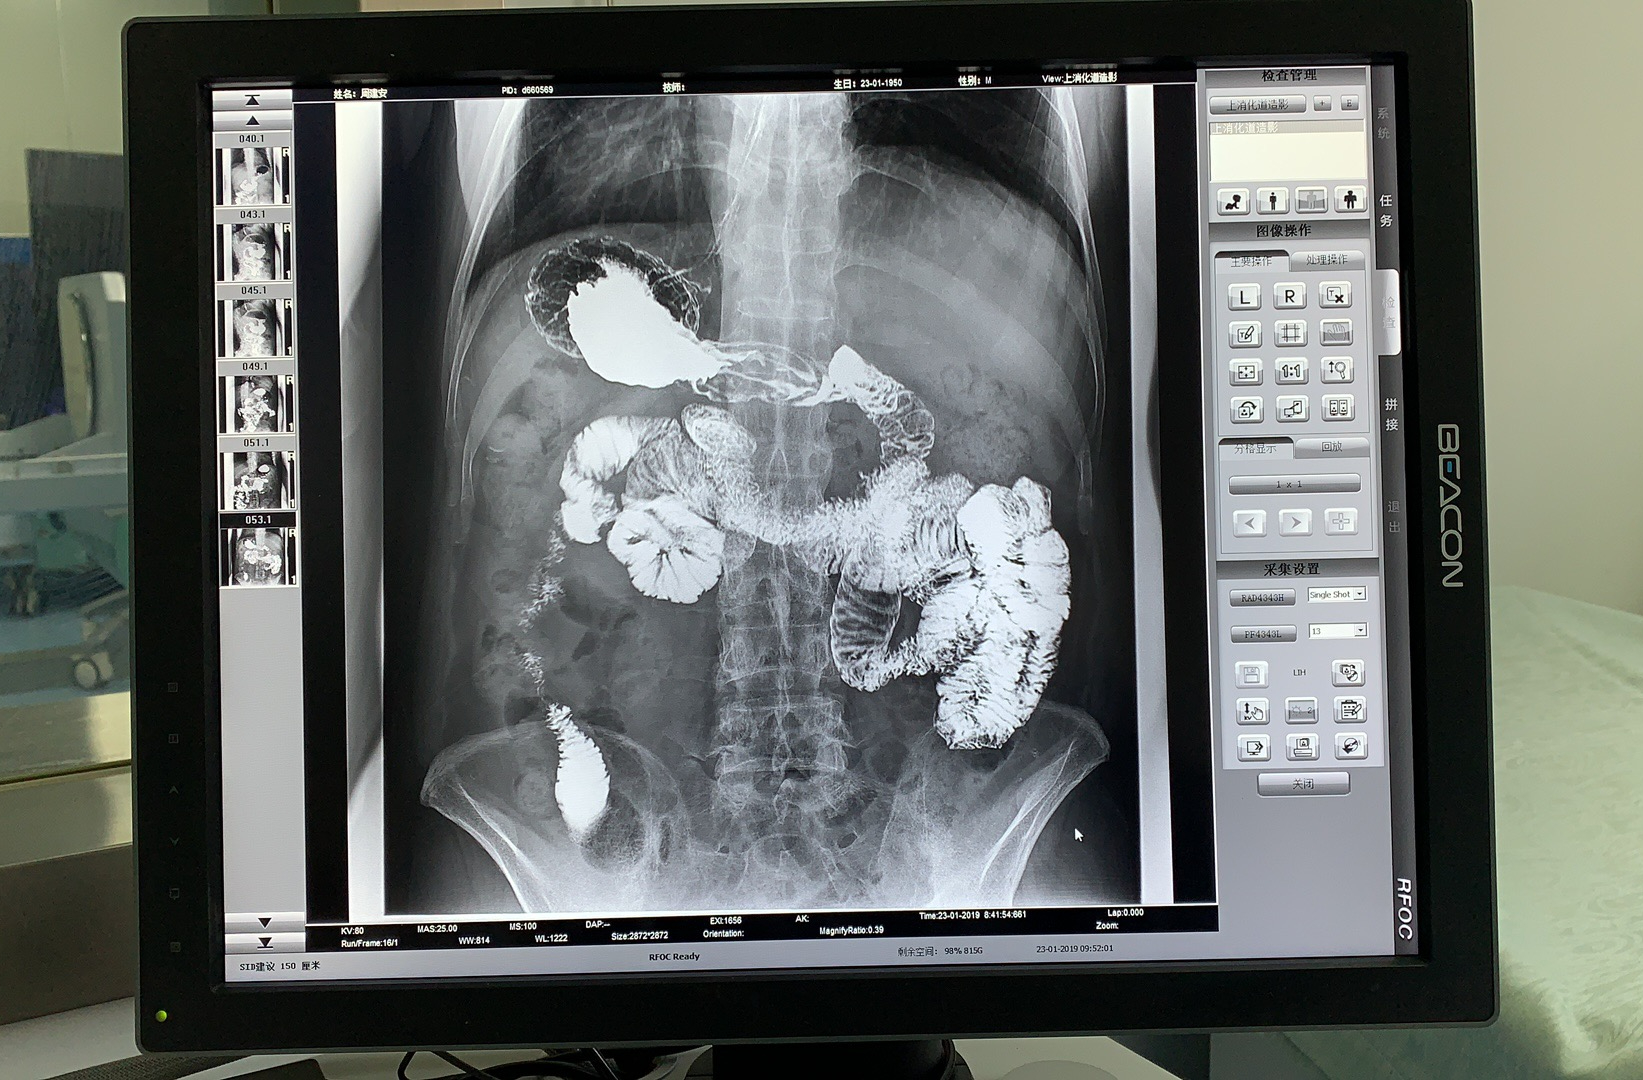

X 線檢查是肛腸疾病早期發(fā)現(xiàn)和診斷最有效的手段之一,隨著數(shù)字化技術(shù)的發(fā)展,可視化動態(tài)DRF的出現(xiàn)為肛腸疾病患者帶來了更加精準(zhǔn)、舒適、方便的檢查方式。